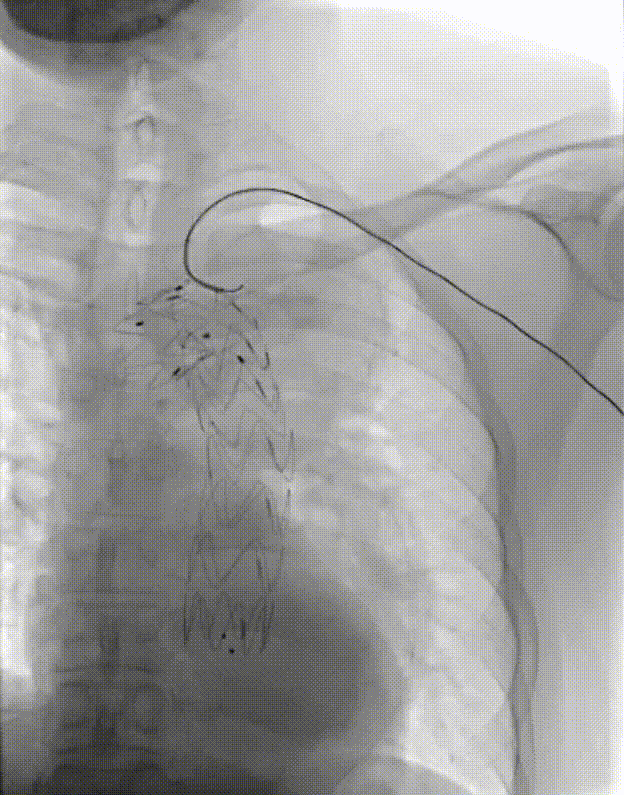

弓部小弯侧动脉瘤,外院TEVAR后IA型内漏

再干预方案:弹簧圈栓塞

弓上分支重建+

近端延伸支架

瘤腔内弹簧圈栓塞